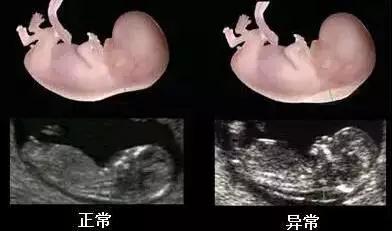

NT即 nuchal translucency 的缩写,它指的是胎儿的 “ 颈项透明层 ”,也就是指胎儿颈椎水平冠状切面皮肤至皮下组织之间的最大厚度,其实就是指胎儿颈后部皮下组织内液体积聚的厚度。

通常用的判断指标:妊娠11-14周+6天时,NT ≥ 2.5毫米视为异常。

NT增厚越明显,发生胎儿结构异常与染色体异常的概率越大。